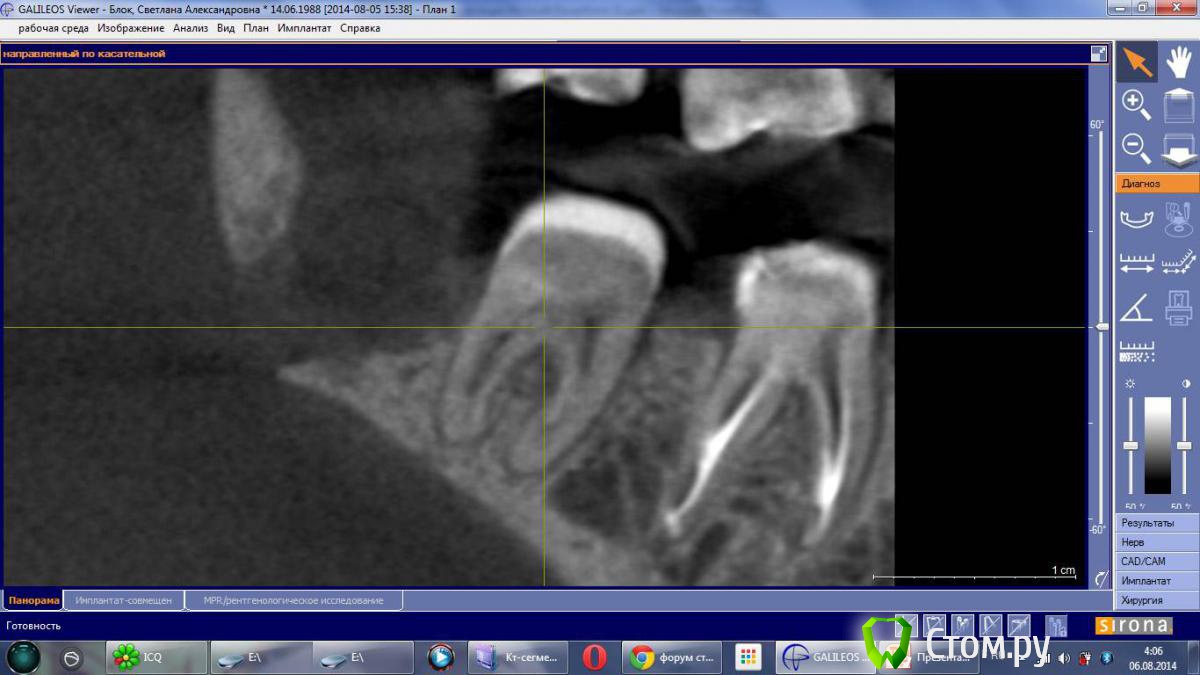

dr-krasnov Опубликовано 3 августа, 2014 Поделиться Опубликовано 3 августа, 2014 (изменено) пано из КТhttp://s014.radikal.ru/i328/1408/c9/c874f56fb9e3.jpg Вот через дистальный корень 47, диск почему-то не совсем корректно открылся. Что смог получить . . . http://s017.radikal.ru/i402/1408/a7/c1f80c5a6231.jpg Изменено 3 августа, 2014 пользователем dr-krasnov Ссылка на комментарий

Lana54rus Опубликовано 5 августа, 2014 Автор Поделиться Опубликовано 5 августа, 2014 Беспокоиться стоит. Если 48 удалён в начале мая, кюретаж 3 недели назад, снимок сделан до кюретажа (когда?) , то я бы посоветовал сделать ещё один хороший прицельный снимок в обл 47 и удалённого 48.Спасибо за внимание к моей теме!Снимок был сделан 7 июля, кюретаж лунки и удаление фрагментов 48 зуба 11 июля. А само удаление 48 зуба было проведено 30 апреля. Сегодня сделала сегментный кт области 47 и 48 зубов. Жду ваших мнений, заранее спасибо!ссылка на сегмент.кт http://www.fayloobmennik.net/4004405 пароль 83834161697 Ссылка на комментарий

Lana54rus Опубликовано 5 августа, 2014 Автор Поделиться Опубликовано 5 августа, 2014 Решила упростить задачу, и сделала скриншоты Ссылка на комментарий

Korel Опубликовано 16 августа, 2014 Поделиться Опубликовано 16 августа, 2014 http://s017.radikal.ru/i442/1408/9f/703a744e8d1b.jpg http://i066.radikal.ru/1408/8d/fb6adabf986c.jpg http://s018.radikal.ru/i522/1408/b2/e3ce4e7db059.jpg Коллеги, на секвестр не похоже? Или ошибаюсь? Исключить остеомиелит, перелом, а затем если не подтвердиться заняться 47? Ссылка на комментарий